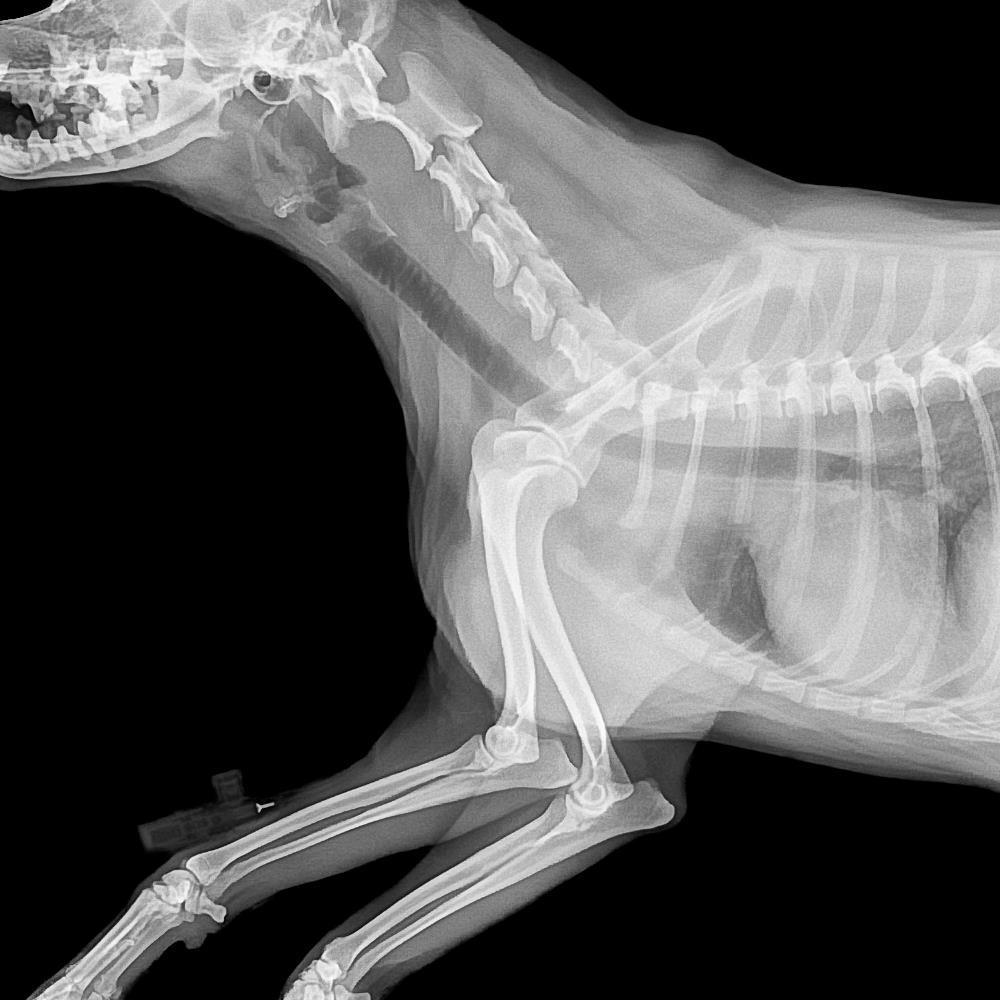

Maslak Vet Zoo, evcil hayvanlarınızın sağlık sorunlarını hızlı ve doğru bir şekilde teşhis etmek için ileri görüntüleme teknolojilerinden biri olan bilgisayarlı röntgen (CR) hizmeti sunmaktadır. Dijital röntgen cihazlarımız, geleneksel yöntemlere göre daha net görüntüler sağlar ve bu sayede hastalıkların tespitinde büyük bir avantaj sunar.

Bilgisayarlı röntgen, kemik kırıkları, çıkıklar, eklem rahatsızlıkları, iç organ problemleri, yabancı cisim varlığı ve dental sorunlar gibi birçok durumun teşhisinde kullanılır. CR teknolojisi, görüntülerin anında dijital ortamda işlenmesine olanak tanır. Bu sayede veteriner hekimlerimiz, hastalığın tanısı ve tedavisi için gerekli adımları hızla planlayabilir.

Maslak Vet Zoo’da bilgisayarlı röntgen işlemi sırasında evcil dostlarınızın güvenliği önceliğimizdir. Kullanılan modern cihazlar sayesinde minimum radyasyon maruziyeti sağlanır ve işlem son derece kısa bir sürede tamamlanır. Çoğu durumda sedasyon veya anestezi gerekmez; ancak hayvanınızın durumuna göre konforunu artırmak için özel uygulamalar yapılabilir.

CR teknolojisi ayrıca görüntülerin saklanmasını ve gerektiğinde diğer veteriner uzmanlarıyla paylaşılmasını kolaylaştırır. Bu, özellikle karmaşık durumlarda ikinci bir görüş almak veya ileri tedavi süreçlerini desteklemek için önemli bir avantajdır.